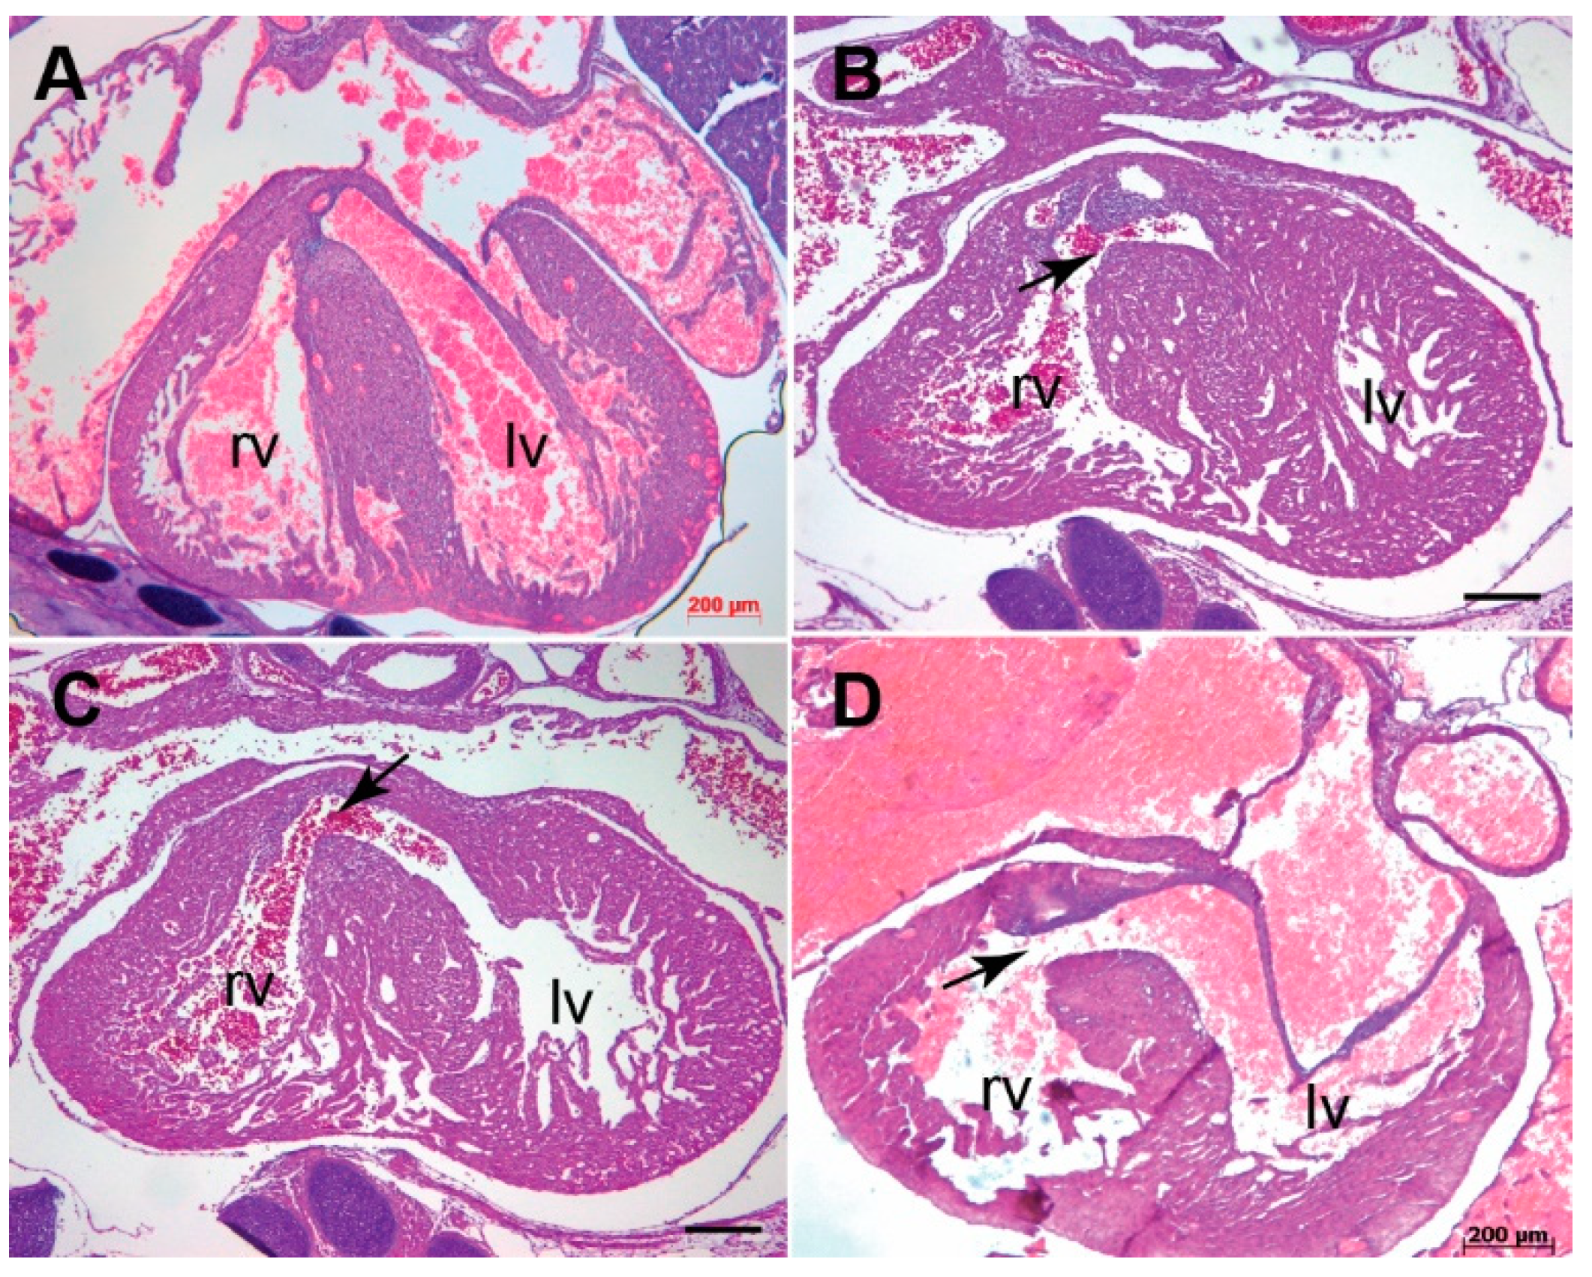

3.1. Systemic Tgfb3 Deletion Disrupts Cardiac Development